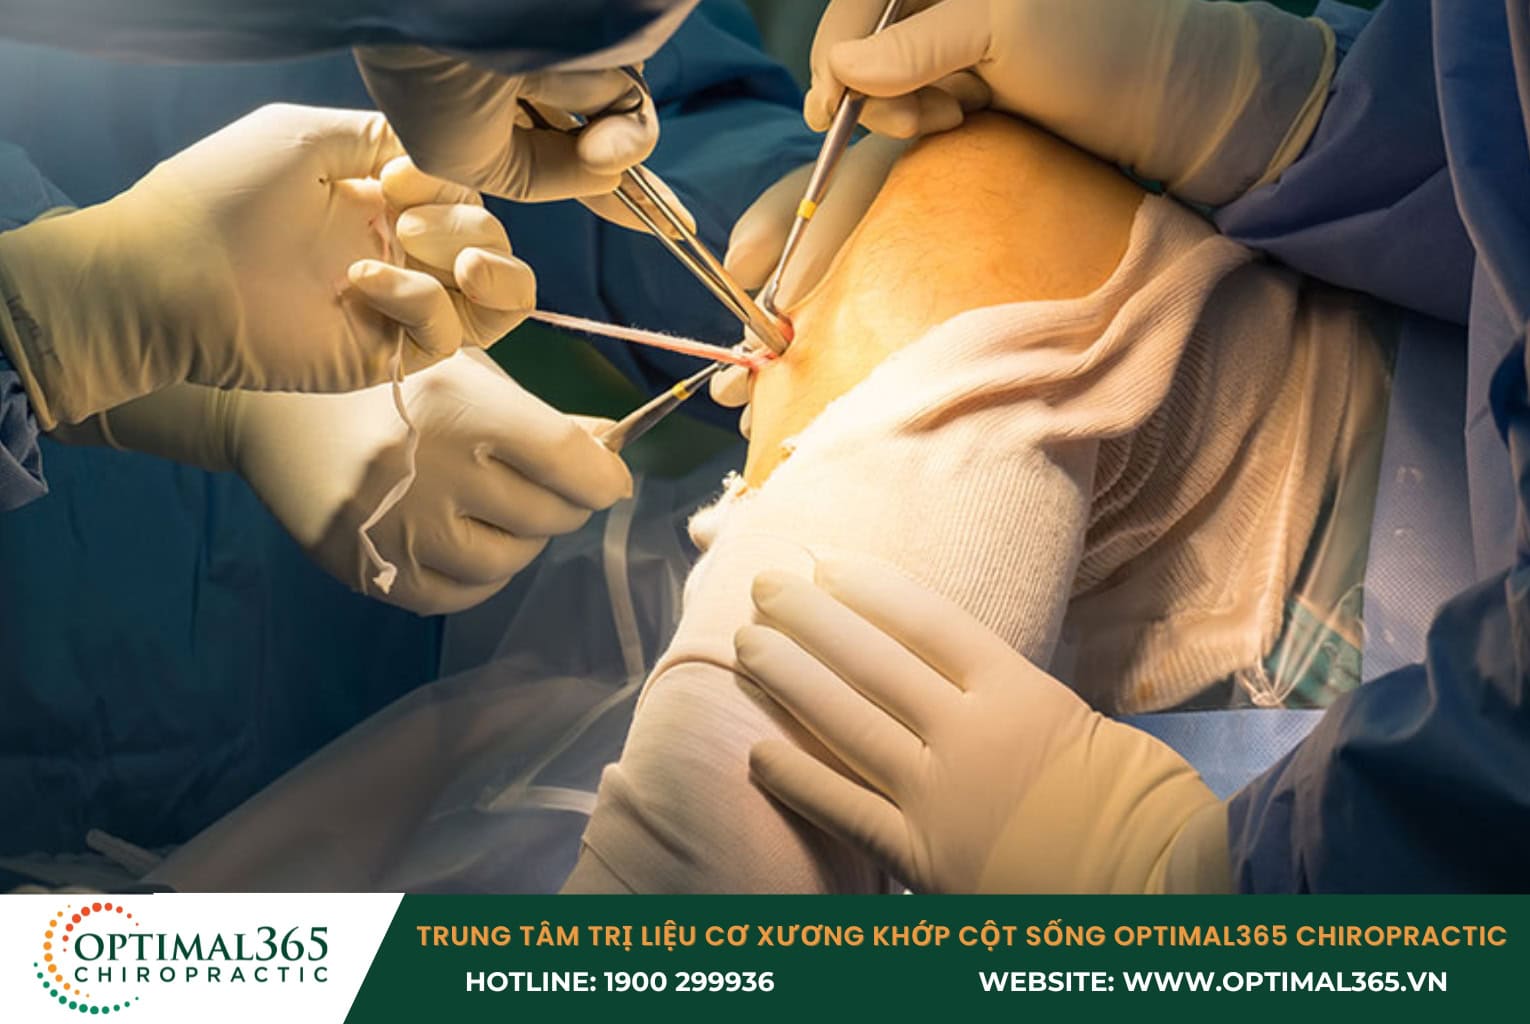

Điều trị phẫu thuật

Trước khi tiến hành phẫu thuật tái tạo dây chằng chéo trước, bác sĩ sẽ thực hiện đánh giá kỹ lưỡng tình trạng tổn thương thông qua hình ảnh MRI và kiểm tra lâm sàng. Phẫu thuật này có thể sử dụng các loại vật liệu khác nhau, bao gồm:

- Vật liệu tự thân: Lấy từ chính cơ thể bệnh nhân.

- Vật liệu đồng loại: Lấy từ người hiến tặng.

- Vật liệu tổng hợp: Sử dụng các chất liệu nhân tạo.

Phẫu thuật có thể mang lại hiệu quả cao trong việc phục hồi chức năng khớp gối. Tuy nhiên, bệnh nhân cần lưu ý rằng mọi thủ thuật ngoại khoa đều tiềm ẩn một số rủi ro như nhiễm trùng, hạn chế vận động khớp hoặc tràn dịch khớp. Vì vậy, việc chỉ định phẫu thuật sẽ được cân nhắc kỹ lưỡng dựa trên tuổi tác, mức độ hoạt động, tình trạng sức khỏe tổng thể và mức độ tổn thương của từng bệnh nhân.

Lưu ý: Bệnh nhân và người nhà không nên tự chẩn đoán hay tự ý điều trị khi không có chuyên môn. Dù chấn thương dây chằng đầu gối ở mức độ nhẹ hay nặng, việc thăm khám tại các cơ sở y tế có trang thiết bị hiện đại và được bác sĩ chuyên khoa kiểm tra là rất cần thiết để đảm bảo phương pháp điều trị chính xác và hiệu quả.